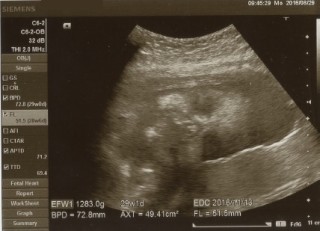

1283gの女の子(予定)です。皆さん赤ちゃん大きいですね。